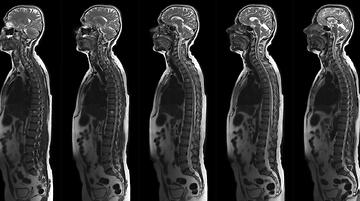

MAGNETKAMERA